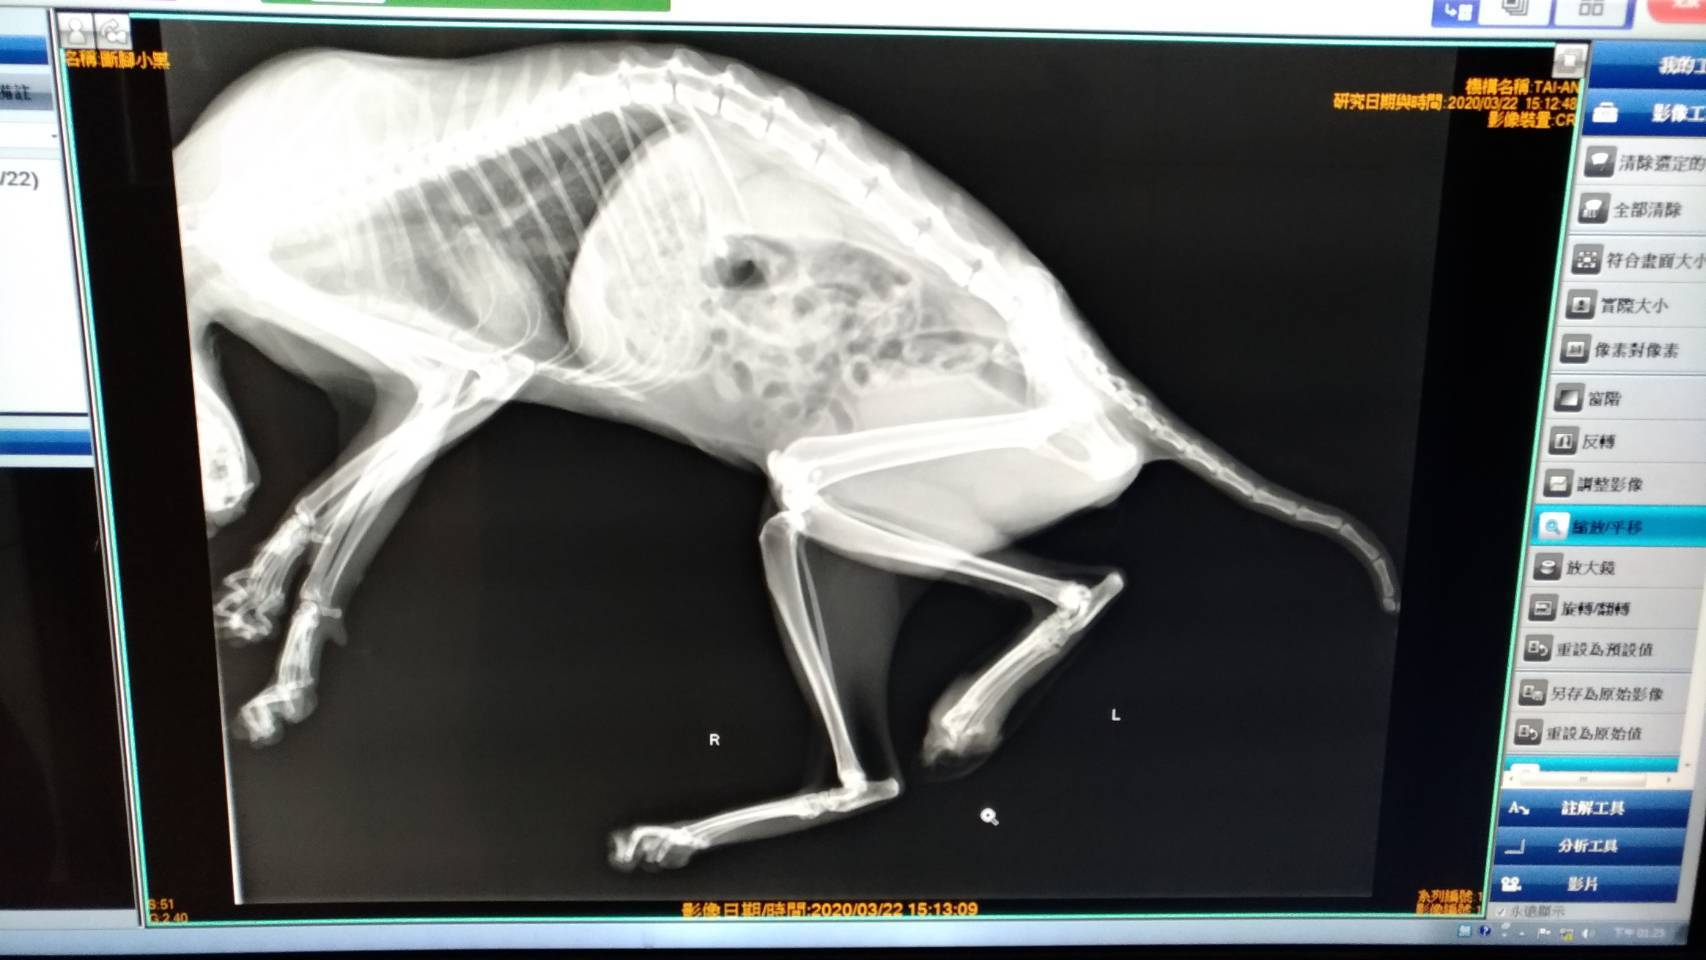

主題: 左腳掌被截斷的黑貓 申請者姓名: shan-chiu Lin 花色: 申請日期: 2020-04-14 14:44:44 申請者部落格: 申請者臉書網址: shan chiu lin 所在縣市/合作醫院: 高雄市/泰安動物醫院 治療費用: 8950元 需求人數: 38人 已結案 (2024-05-31 18:18:47) 報名人員: Andrea Hsieh(已付款)、Munnies x2(已付款)、YiLing Li x3(已付款)、Gloria Wu x3(已付款)、jajamama x3(已付款)、順治 x2(已付款)、香香大爺 x5(已付款)、Jen(已付款)、Funyee(已付款)、Rachel Hsieh x3(已付款)、Vincenthsu(已付款)、王員外的爹 x10(已付款)、王員外的爹 x3(已付款)、 候補人員: 動物病情說明: giordano是我在仁愛國小另一側餵養的街貓

醫生檢查發現左腳掌只剩大拇指

一節趾骨露出需開刀拿掉

幸好目前未發現有深層感染

應該不需要截肢